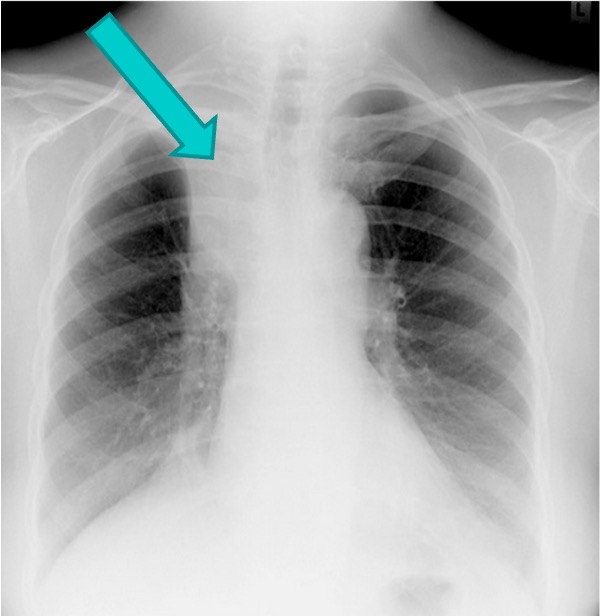

Tuberculosis

Caused by Myobacterium tuberculosis

Spreads mainly by droplets in the air

Primarily a disease of the lungs but can spread to GI, GU, and skeletal system